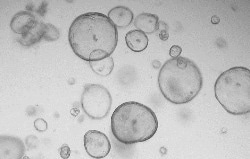

Human liver cancer organoids

Human liver cancer organoids were cultured with FGF2 (Cat#: 10014-HNAE), HGF (Cat#: 10463-HNAS), FGF7 (Cat#: 10210-H07E), EGF (Cat#: 50482-MNCH), FGF10 (Cat#: 10573-HNAE), TGFB1 (Cat#: 10804-HNAC), NOG (Cat#: 50688-M02H), and RSPO1 (Cat#: 11083-HNAS). Image Credit: Sino Biological US Inc.